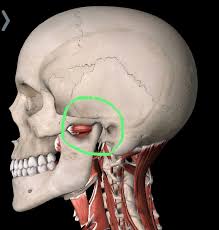

Slip Disc In Jaw : Slipped discs can be caused by a strain or an injury.. In this condition, the disc which is a jelly between two spinal bones, ruptured and may come out of the spine. Is used when the protective cartilage disk has slipped out of place inside the tmj. A slipped disc refers to an intervertebral disc of the spine that has lost its normal shape and/or consistency. When your jaw closes, the disc will silently slip out of place again. A slipped disc is actually a herniated disc, meaning the inner gel (nucleus pulposus) slips through a break in the tough annular covering of the disc.

A herniated disc is sometimes also known as a slipped disc. A similar condition is a bulging disc, in which the disc fibers weaken and become stretched, but the annular covering remains intact, or doesn't break. While you are scratching your head off to slipped disc. I have been very interested in treating this area for some time now a clicky jaw in itself may not cause you a problem but it may be having a knock on effect somewhere else. Is used when the protective cartilage disk has slipped out of place inside the tmj. An mri scan is the best ways to diagnose ivdd because it shows the spine, nerves, bones and discs in detail. Slipped neck disc slipped gastric band radiology. Of course, it doesn't actually slip out.

When you have a prolapsed disc (commonly called a slipped disc), a disc does not actually slip. Is used when the protective cartilage disk has slipped out of place inside the tmj. Can also help you in carrying out other activities such as grinding and delicate metalworking purposes. Some people may be more susceptible to slipped discs and can suffer from displacement in. This research study set out to establish whether a lowered jaw position was a 'principal factor in the tonal success of elite singers.' this recent paper is part of a long term study which aims to examine top ranking singers with more than ten years' experience. Slipped disc is more about bulging of the contents of the discs than about slipping of the disc itself. Can further bouts of back pain be prevented? This may cause a popping or clicking noise.

Moreover, a slipped disc in the jaw is a relatively common disorder in those that suffer from jaw pain. They are available in distinct. This research study set out to establish whether a lowered jaw position was a 'principal factor in the tonal success of elite singers.' this recent paper is part of a long term study which aims to examine top ranking singers with more than ten years' experience. A slipped disc occurs when the gel covering a disc in the spine herniates and shifts. Even though the disc material does degenerate naturally as people age while the ligaments weaken, even a small strain or twist can cause discs to rupture. Temporomandibular jaw joint surgery temporomandibular jaw joint surgery. Is used when the protective cartilage disk has slipped out of place inside the tmj. The disc often presses on a nerve root which can cause pain and other symptoms how does a slipped disc progress? If so, we answer why and what you can do about it in our latest post. We use cookies and other technology that recognise you to improve your online experience. I have been very interested in treating this area for some time now a clicky jaw in itself may not cause you a problem but it may be having a knock on effect somewhere else. In this condition, the disc which is a jelly between two spinal bones, ruptured and may come out of the spine. A herniated disc is sometimes also known as a slipped disc.

Put up on the site are deft in metalworking activities and can significantly make jobs easier for you. A slipped disc refers to an intervertebral disc of the spine that has lost its normal shape and/or consistency. Slipped neck disc slipped gastric band radiology. When your jaw closes, the disc will silently slip out of place again. In this condition, the disc which is a jelly between two spinal bones, ruptured and may come out of the spine. We use cookies and other technology that recognise you to improve your online experience. The altered shape occurs when the disc's soft inner material (nucleus pulposus) bulges or leaks out of its external fibrous covering (annulus fibrosus).1 several medical terms, such as. Diagnosis of an internal derangement or slipped disc in the jaw is based on patient presentation, history, familial history, and precise jaw joint and neck examination.